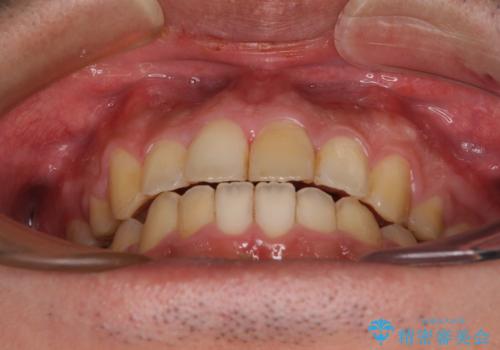

後戻りでデコボコの前歯 インビザライン矯正治療

下顎骨が左側に変位しているため、正中が合わないことは予想できましたが、歯列が整った後も咬み合わせが安定せず、咬み合わせを落ち着かせるために1年以上の期間を要しました。

噛みにくさの改善に時間がかかってしまうことがインビザラインの欠点の1つといえます。